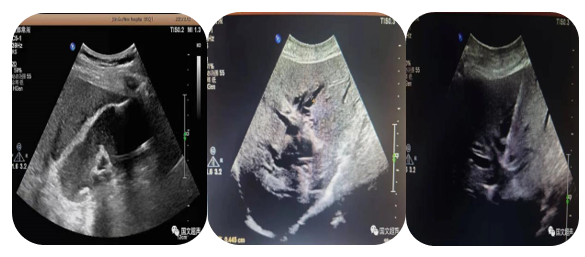

3.超聲引導下經(jīng)皮經(jīng)肝膽道置管引流、膽囊造瘺;經(jīng)皮腎造瘺、膀胱造瘺

超聲實時引導下將引流管放置在因腫瘤、結石等壓迫、堵塞梗阻擴張的膽道、腎盂、膽囊、膀胱內(nèi)引流出潴留的膽汁、尿液,防止或緩解肝腎功能衰竭,進而減緩患者痛苦為臨床爭取治療機會。

經(jīng)皮經(jīng)肝膽囊造瘺、膽道置管引流

經(jīng)皮腎造瘺

經(jīng)皮膀胱造瘺